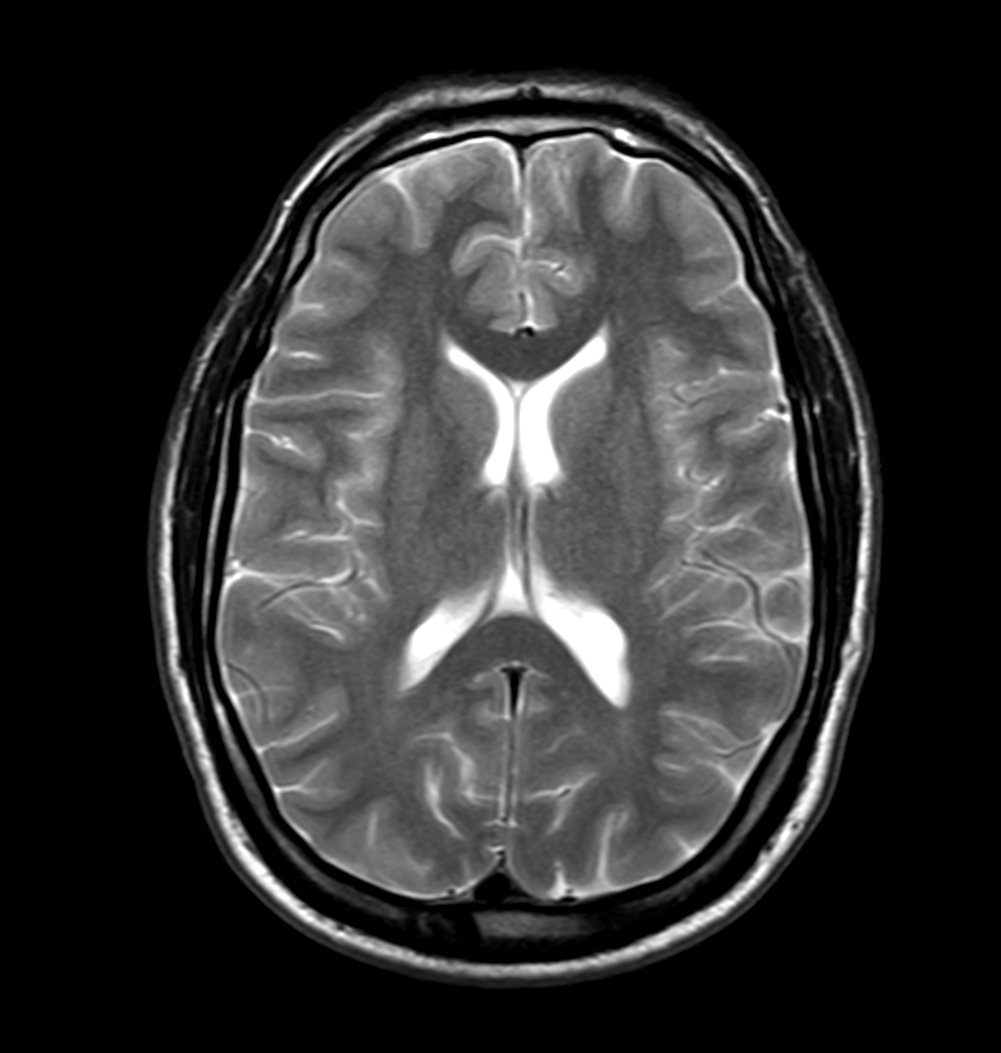

Axial T2w mDIXON XD - T2w TSE (Water only)

Axial T2w mDIXON XD - T2w TSE (In Phase)